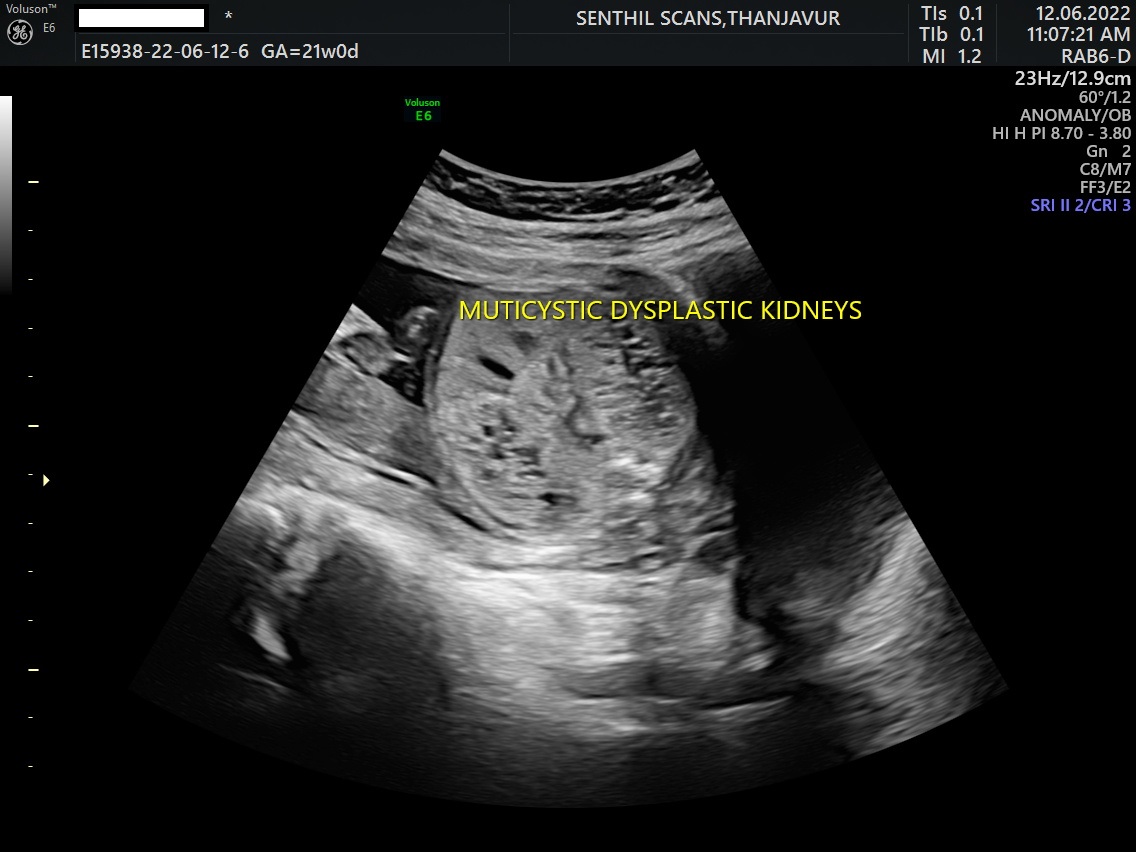

Modern, imported, high end, state of art machines. (Ultrasound, CT scan, MRI scan, Mammogram, etc.)

Accurate reports with all fine details of investigations.

Senthil Scans offers the region’s most comprehensive range of diagnostic services, from MRI to X-ray.